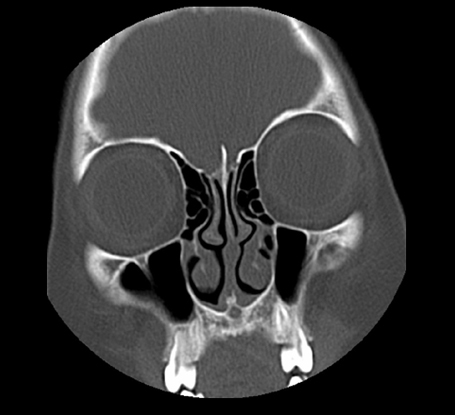

Head and Neck Radiology CT Coronal

CT Coronal